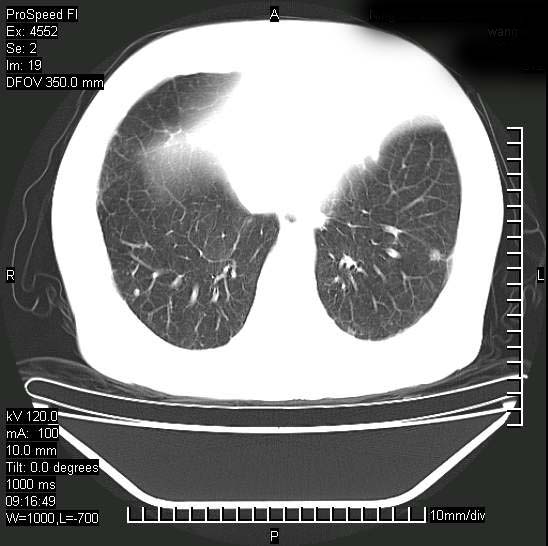

[face=黑体]8月30日[/face]

十几年前曾患肺结核,一周前突咳血约100ml,中性粒细胞稍高,诊断两上肺陈旧结核,下肺炎症,给予抗炎治疗,近几日晚上高热,39度,仍咳少量血,4天前ct及今天ct上传。